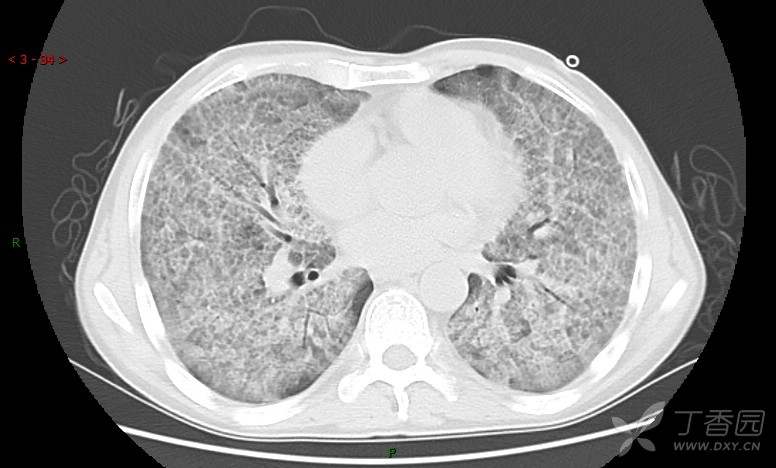

地图+铺路石征=PAP?那升高的CEA怎么说(病例3连发,附其他2例链接)

患者男,42岁,咳嗽半年余,加重伴憋喘2月余。

患者半年余前无明显诱因出现间断咳嗽,干咳为主,偶咳少量黄白痰,剧烈咳嗽或运动后可出现轻度憋喘,无高热、脓臭痰,无胸痛、咯血及晕厥,无低热乏力及盗汗,无心前区压榨感及夜间阵发性呼吸困难,初未在意,未予正规诊治。2月余前患者自觉上述症状较前加重,咳嗽、憋喘明显,黄白色粘痰略有增多,伴有发热,热前伴有畏寒、寒战,体温最高达38.9℃,先后就诊多家医院,入住重症监护室,未行气管插管,考虑“重症肺炎”,给予“美罗培南、复方磺胺甲噁唑”等药物抗感染,“卡泊芬净”抗真菌,并给予“甲泼尼龙”等药物治疗35天,经治疗后症状好转于2018-04-02出院。患者自出院后仅应用中药治疗(具体不详),并给予家庭氧疗,平素仍有间断咳嗽,咳少量黄白色粘痰,活动后憋喘明显,活动耐量差,以卧床为主。

肺内弥漫性网状结节影,PET-CT却无阳性病灶,这是?(附其他2例链接)